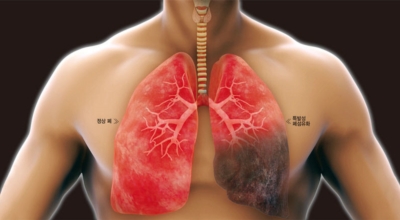

폐렴을 유발하는 페렴구균은 일반인 40%가 이미 갖고 있다고 하네요. 평상시에는 해가 없다가 면역력이 줄어들게되면 폐렴이 발병하는데 이 때에 폐에 산소가 부족하게 되면서 청색증이 타나날 수 있다고 하며 손, 발, 입술 처럼 피부가 얇은 곳이 새파랗게 변하게 된니다.

폐에 염증이 생기면 폐를 구성하는 세포가 파괴되어 정상적인 산소를 저장할 수 없게 됩니다. 따라서 폐렴 증상이 나타나면 호흡 곤란을 겪는 경우가 많습니다.